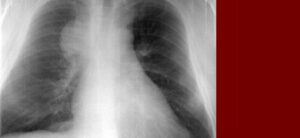

Рак дыхательных путей является третьей по значимости причиной смерти в Европе. С каждым годом количество заболевших постоянно увеличивается. Рак средостения легкого — одна из редких, но очень опасных форм. Заболевание характеризуется быстрым ростом опухолевых клеток в органах средостения. Общая информация Рак легкого средостения — один из атипичных видов рака дыхательной системы. Для этого вида онкопатологии …